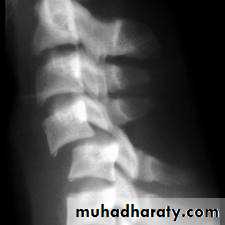

anteriorly and becomes wedge-shaped, giving rise to a localized kyphosis.WEDGE COMPRESSION FRACTURE

The standard method of treatment may, therefore, be said to be conservative.BURST FRACTURE OF A VERTEBRAL BODY

the compression force thus acts vertically in the line of the vertebral bodies.

The intervertebral disc is forced

In the affected vertebral body, causing a comminuted bursting fracture in which fragments are driven outwards in all directions.